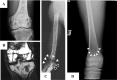

Marrow adipose tissue (MAT) is functionally distinct from both white and brown adipose tissue and can contribute to systemic and skeletal metabolism. MAT formation is a spatially and temporally defined developmental event, suggesting that MAT is an organ that serves important functions and, like other organs, can undergo pathologic change. The well-documented inverse relationship between MAT and bone mineral density has been interpreted to mean that MAT removal is a possible therapeutic target for osteoporosis. However, the bone and metabolic phenotypes of patients with lipodystrophy argues that retention of MAT may actually be beneficial in some circumstances. Furthermore, MAT may exist in two forms, regulated and constitutive, with divergent responses to hematopoietic and nutritional demands. In this review, we discuss the role of MAT in lipodystrophy, bone loss, and metabolism, and highlight our current understanding of this unique adipose tissue depot.